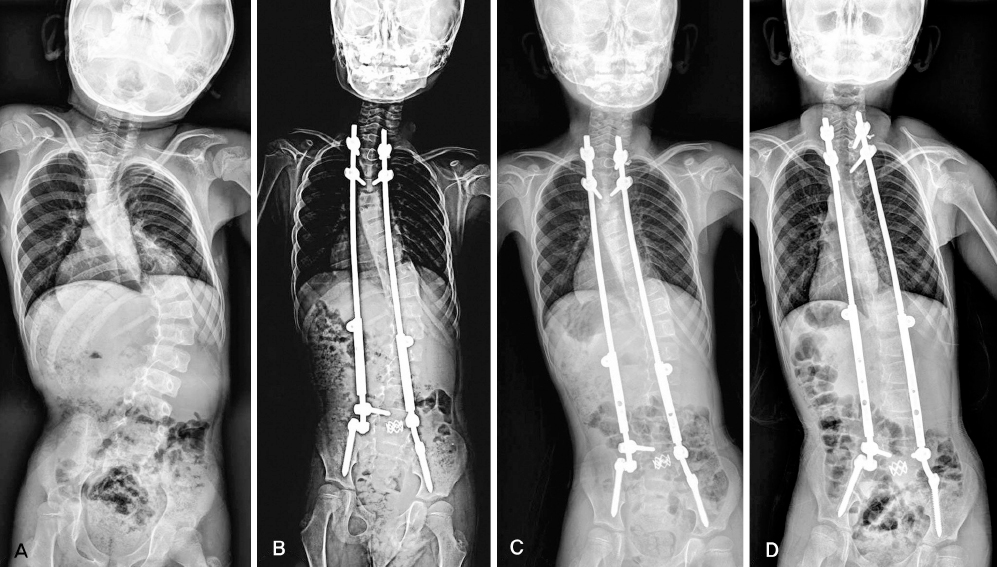

A escoliose é uma patologia que afecta a coluna vertebral, provocando curvatura anormal e deformidades progressivas, sobretudo em crianças e adolescentes. De acordo com Djamel Kitumba, a ausência de diagnóstico e tratamento precoces pode levar, na fase adulta, a complicações graves, incluindo problemas neurológicos, respiratórios e cardíacos, comprometendo a qualidade e a esperança de vida.

Dados apresentados pelo médico indicam que cerca de 8% das crianças e adolescentes angolanos convivem com esta condição.